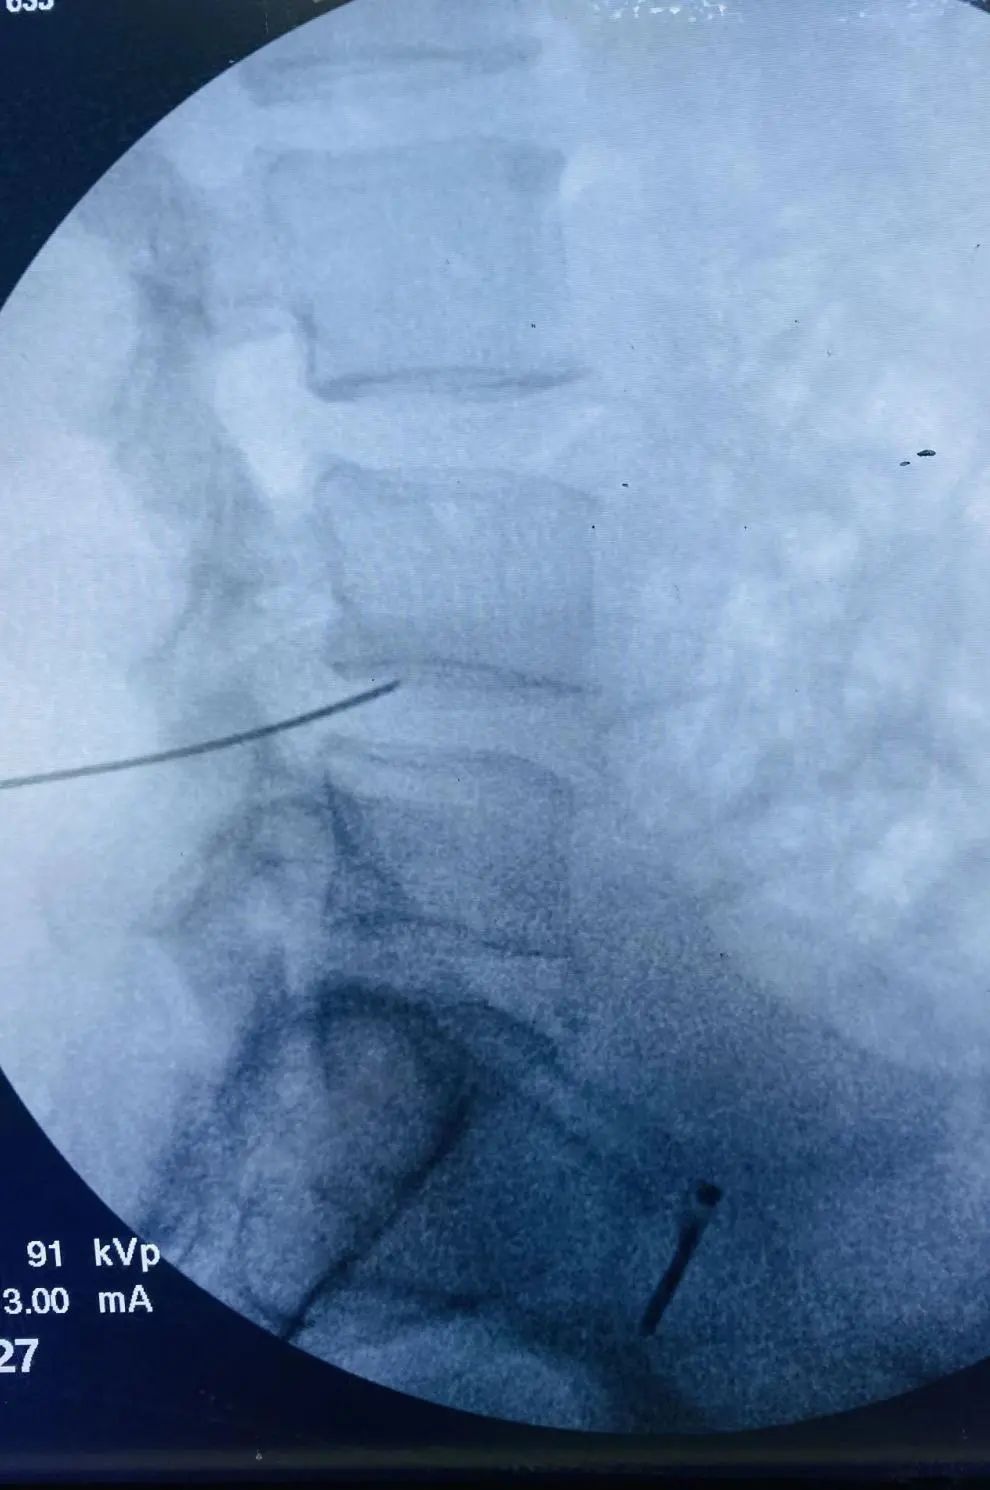

于6月9日在手术麻醉科配合下,脊柱外科管廷进主任医师、孙鹏副主任医师、苏凯主治医师在局部麻醉下为患者实施L4/5椎间盘低温等离子射频消融、椎间盘汽化微创手术,手术顺利,术后患者腰腿痛不适症状即刻缓解。

低温等离子射频消融术的原理是通过等离子刀将射频能量作用于椎间盘内部,汽化消融部分椎间盘髓核组织,然后再利用精确的热皱缩技术将刀头接触到的髓核组织加温至约70度,使髓核体积缩小,降低椎间盘内压力,从而缓解椎间盘突出对神经根的压迫而达到治疗的目的。